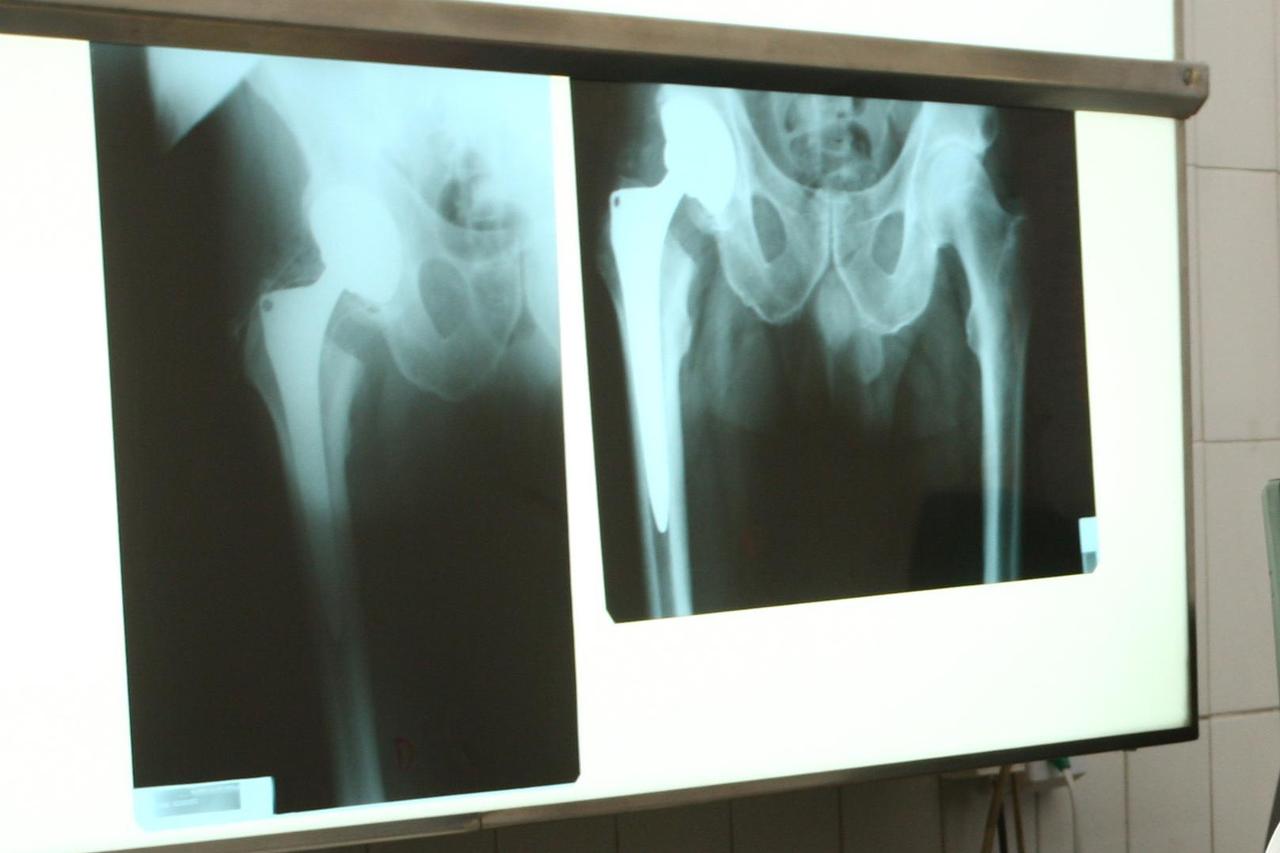

Ortopedi: Ugrađuju kukove, a nemaju licence